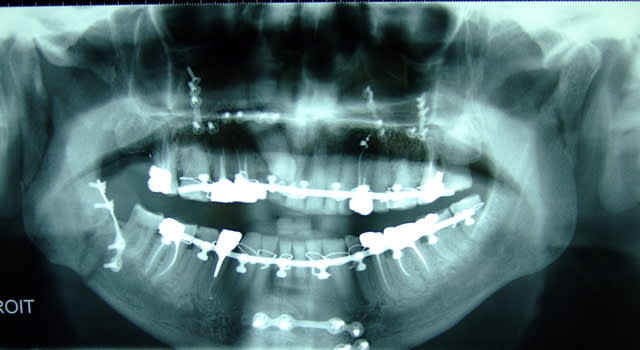

il y a quand même une fracture importante pas du tout réduite à droite.

perso ce qui m embete c est la double frature des condyles sans plaques ni bloquages ...

un panoramique post depose des ligatures peut-etre?

Par contre concernant une éventuelle chir, voilà la démarche qui m'a été donnée :

à traiter comme une dysmorphose dentosquelettique

1 moulage

2 etude de l'occlusion

3 teleradiographie face profil face inf et surtout panoramique.

4 s'assurer de la parfaite consolidation de la mandibule et du maxillaire (choppe l'arcade maxillaire, maintiens le front et remue le tout en force, comme si tu prenais des empreintes : antéropostérieur et rotation. Fais également croquer en anterieur sur des abbaisse-langue pour cherhcer une mobilité du maxillaire et éventuellement du nez !)

Si tout est solide, on peut s'en sortir avec une ostéotomie type lefort I : on vire les synthèses maxillaires, on coupe droit, on impacte un peu en postérieur ou on se sert de la canine incluse (qui a pris des vis je crois et qui risque de se mortifier) pour redonner de la hauteur antérieure. Bien sur un blocage est nécessaire 15 jours puis 1 mois la nuit.

il semble que les baques visibles sur la pano aient au moins servi pdt la chir, meme si la contention interarcade n' a pas été gardée pendant 3 sem... il était pas en ttt ortho ton papy ;) bref...j' ai du mal à croire que le chir n' ait pas utilisé, au moins en per op cet ancrage inter max...par contre, la fracture des condyles, ds l' urgence, n' avait peut etre pas été vue s'il n'y avait sur le moment , de déplacement...et puis, gérer un tel trauma et la bouillie qui allait avec n' avait pas du etre aisé...et j' imagine (car ça ne m'est jamais arrivé), opérer un accidenté doit etre très très loin d'opérer un patient qui "va bien" ...

bref, imaginons qu'il n' y avait pas de deplacement de la fracture des condyles, et qu'elle soit passée inaperçue...alors, ça explique qu'il n' y ait pas eu de plaque d' ostéoS..? la suite peut aussi s' expliquer: la force des masticateurs a créé une surpression postérieure, ce qui a ouvert (déplacé) la fracture bicondylienne, ce qui a ouvert une béance antérieure.

bref, je pense que la béance ant n' étai pas la en per et post op immédiat, et qu' elle résulte du déplacement de la fracture.